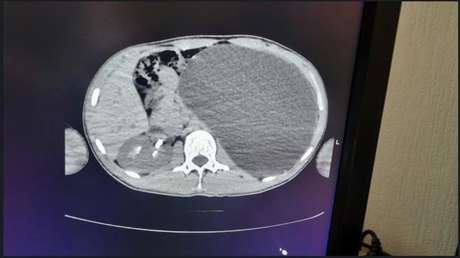

Científicos de todo el mundo unifican criterios para determinar el diagnóstico de muerte cerebral 16 ago 2020, 09:54 GMT